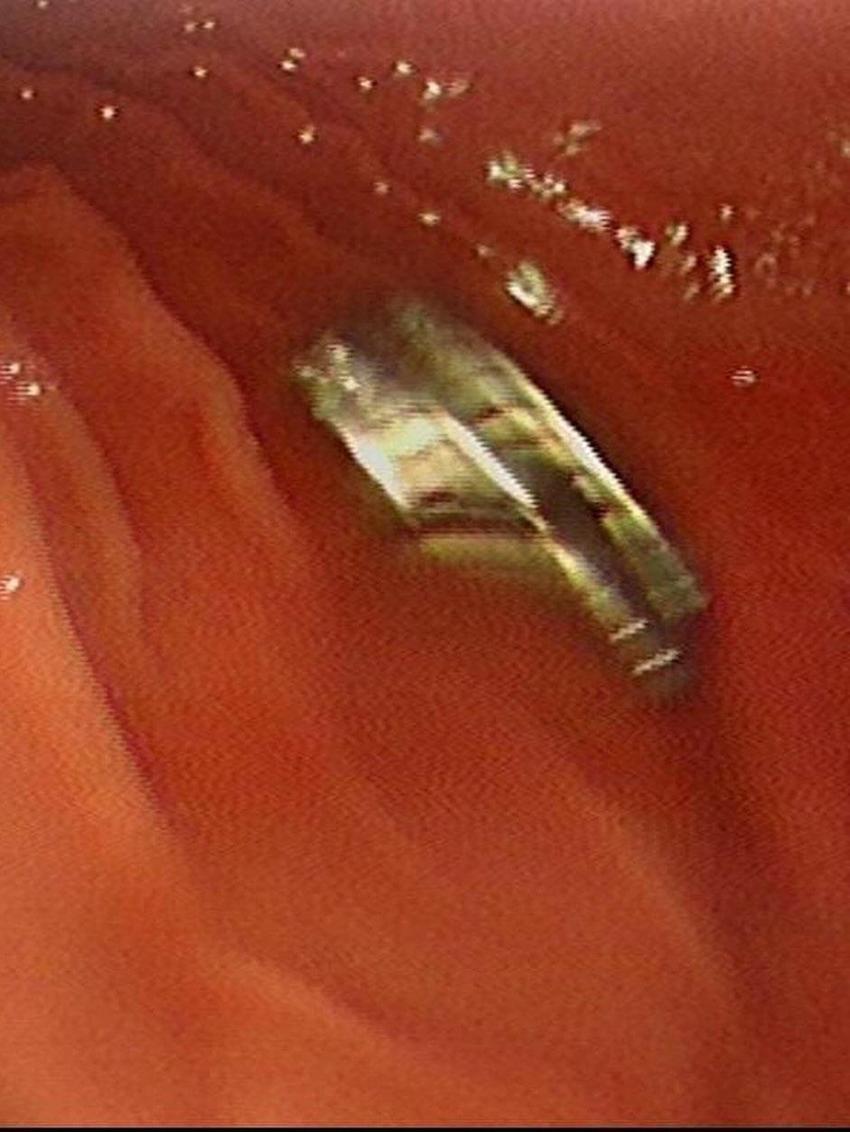

Yapılan ilk müdahalenin ardından çocuk, ileri tetkik ve tedavisi için Elazığ’daki Fırat Üniversitesi Hastanesi’ne sevk edildi. Fırat Üniversitesi Tıp Fakültesi Çocuk Gastroenteroloji, Hepatoloji ve Beslenme Bilim Dalı Başkanı Prof. Dr. Yaşar Doğan ve ekibi tarafından gerçekleştirilen operasyonla, çocuğun yemek borusuna yapışan 19 mıknatıs endoskopik yöntemle çıkarıldı.

Mıknatısların, mide girişinde ve yemek borusunda zedelenmelere yol açtığı belirtildi. Çocuk tedavisinin ardından taburcu edildi.